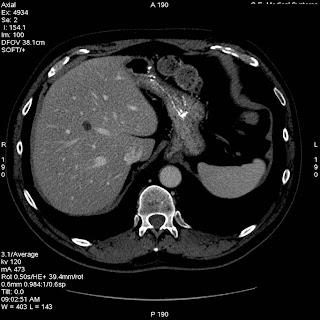

Varón de 63 años que consulta por dolor pélvico y tenesmo rectal de dos meses de evolución

solución